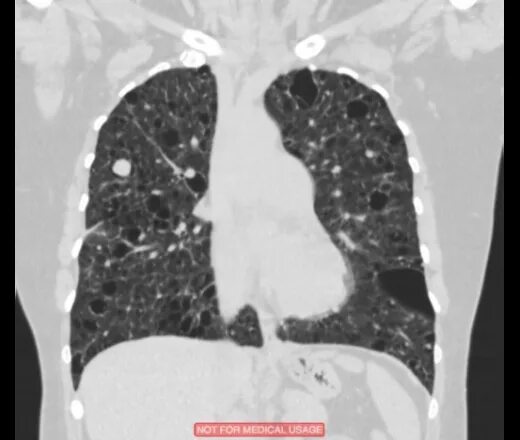

Единичные солидные узелки в легких